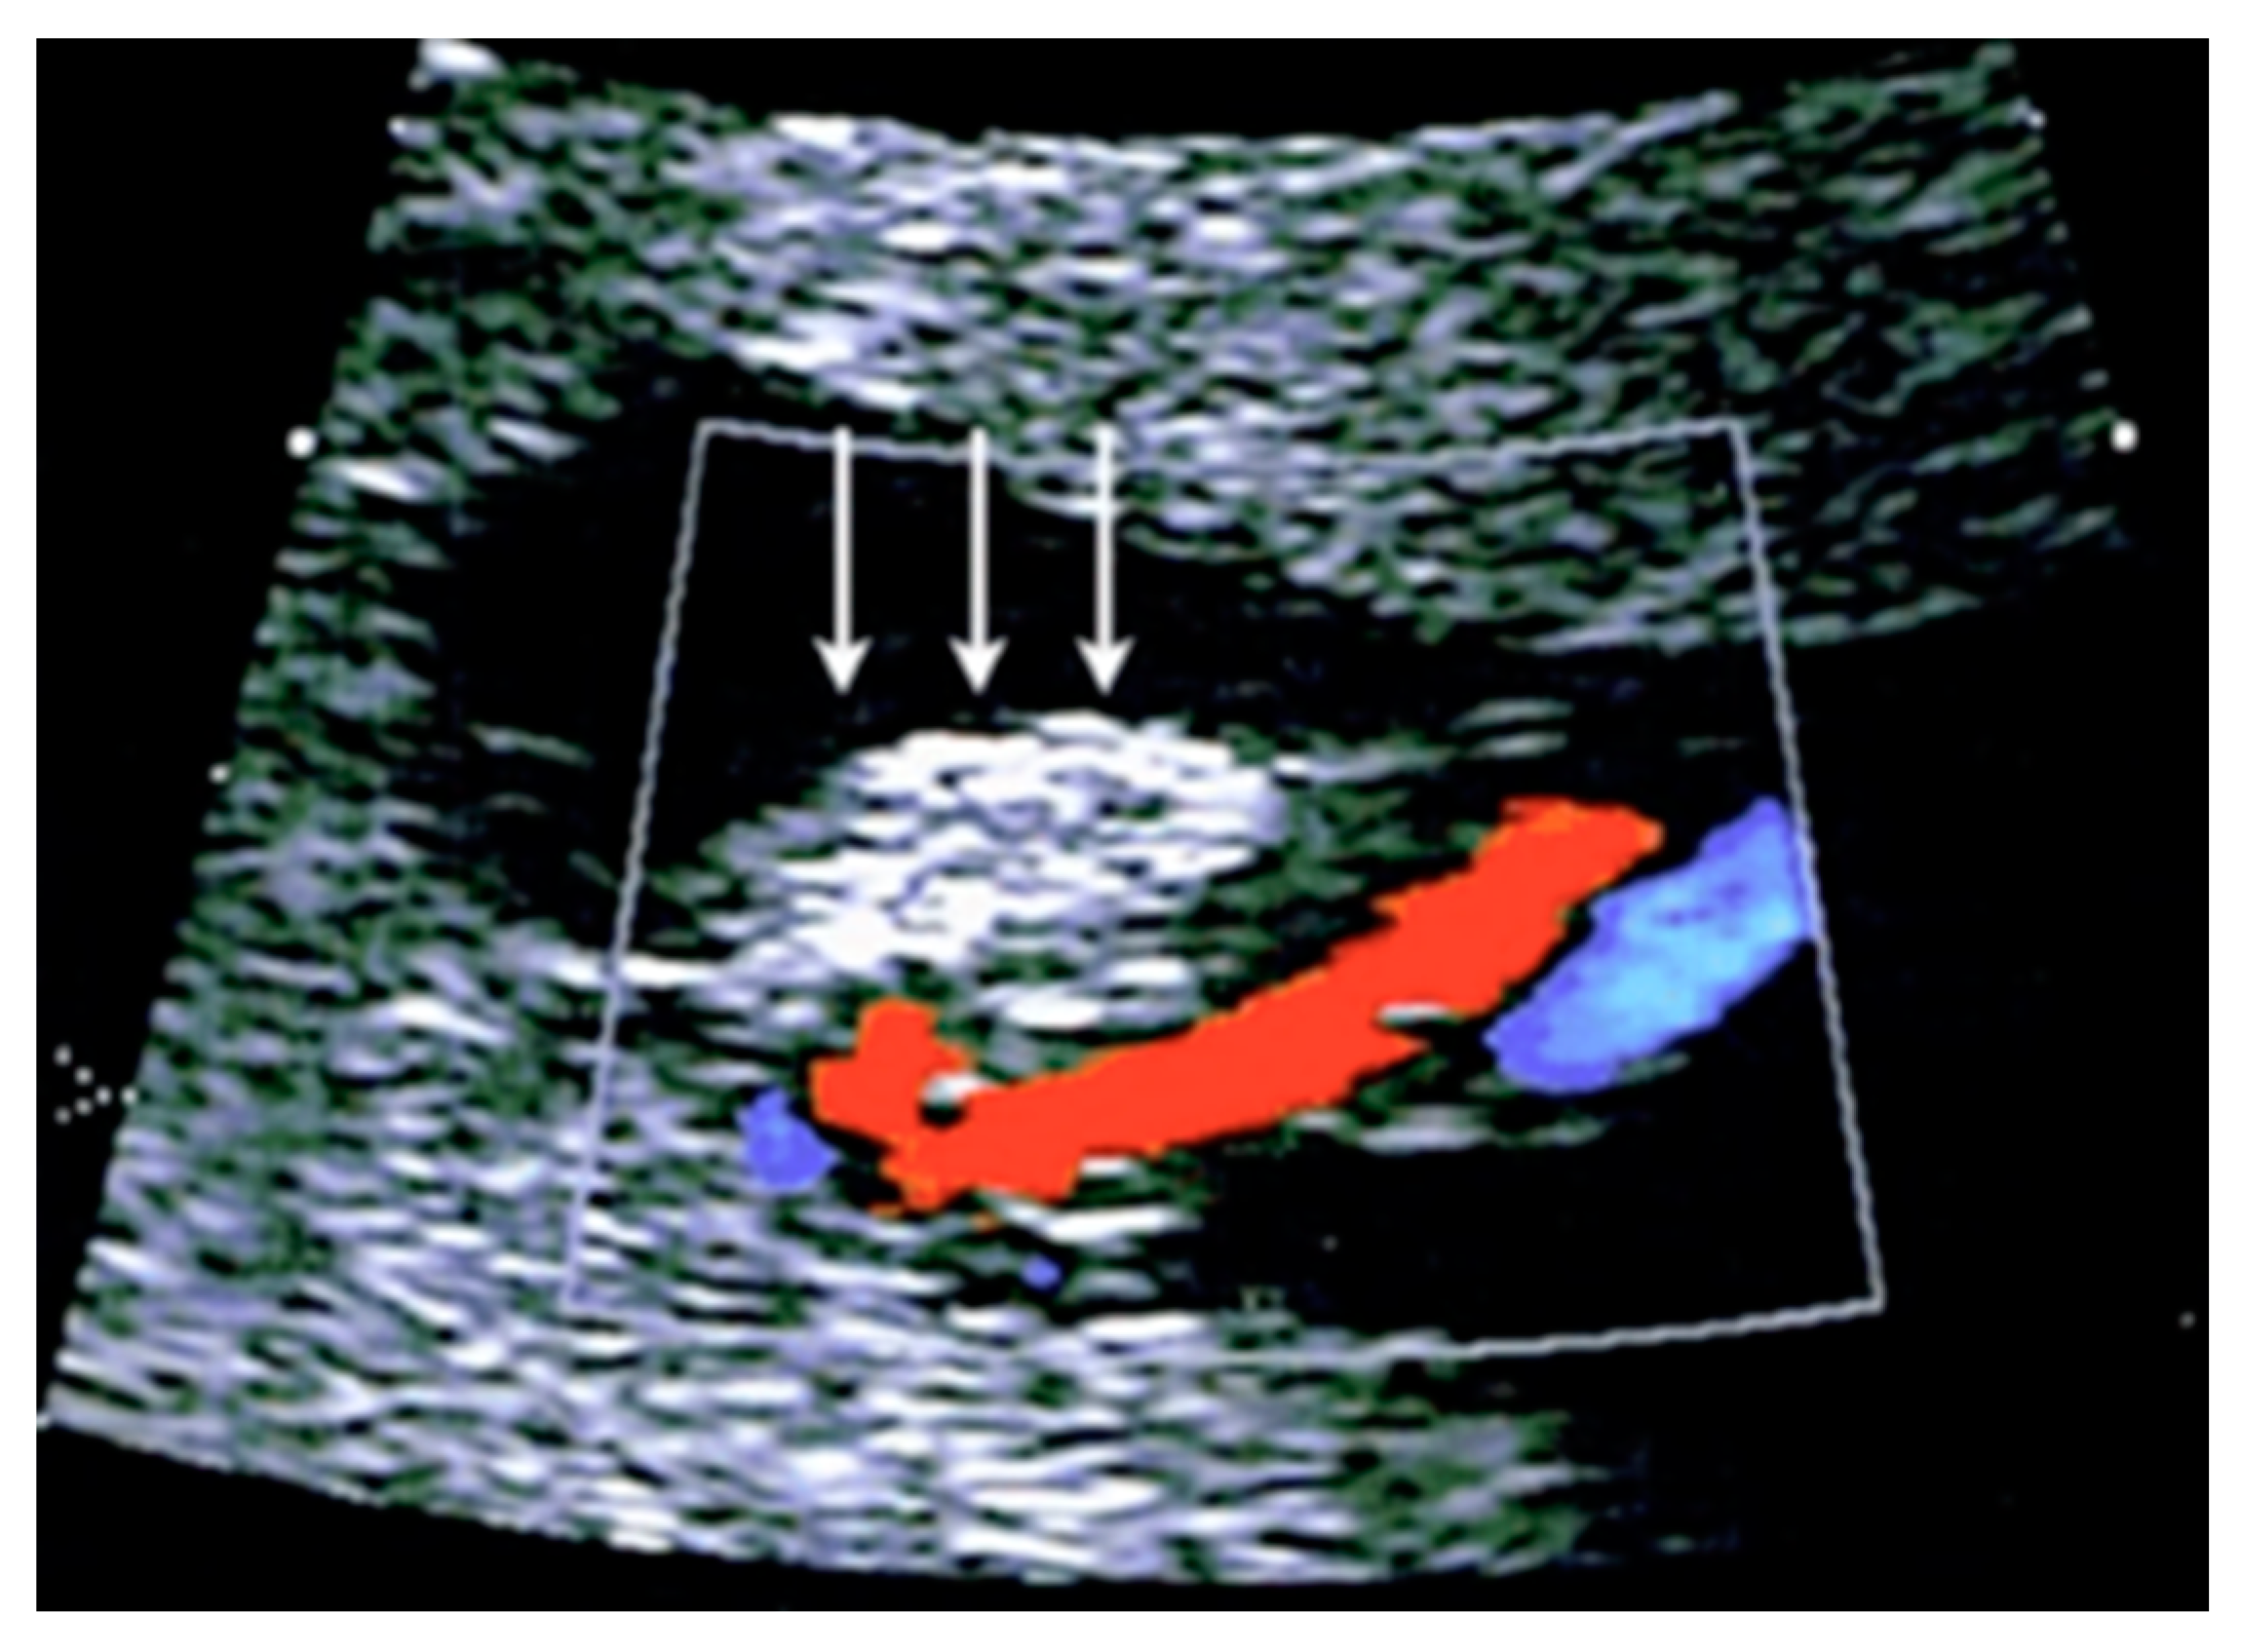

3.2.8. Umbilical Cord Hematoma

Umbilical cord hematomas are rare events that occur in 1:5,500 pregnancies and mostly take place due to the rupture of the umbilical vein rather than the umbilical arteries [64]. They are associated with oligohydramnios and second-trimester amniocentesis, and the compression of the umbilical vessels induced by a cord hematoma can cause fetal hypoxia or intrauterine death in up to 40% of cases [64]. At ultrasound, it appears as a focal mass on the cord without blood flow on color Doppler ultrasound [47,63] (Figure 28).

Figure 28.

Transient umbilical cord hematoma in the cord insertion area on the placenta after intra uterine fetal transfusion (IUFT). Note the absence of blood flow on color Doppler ultrasound assessment (arrows).